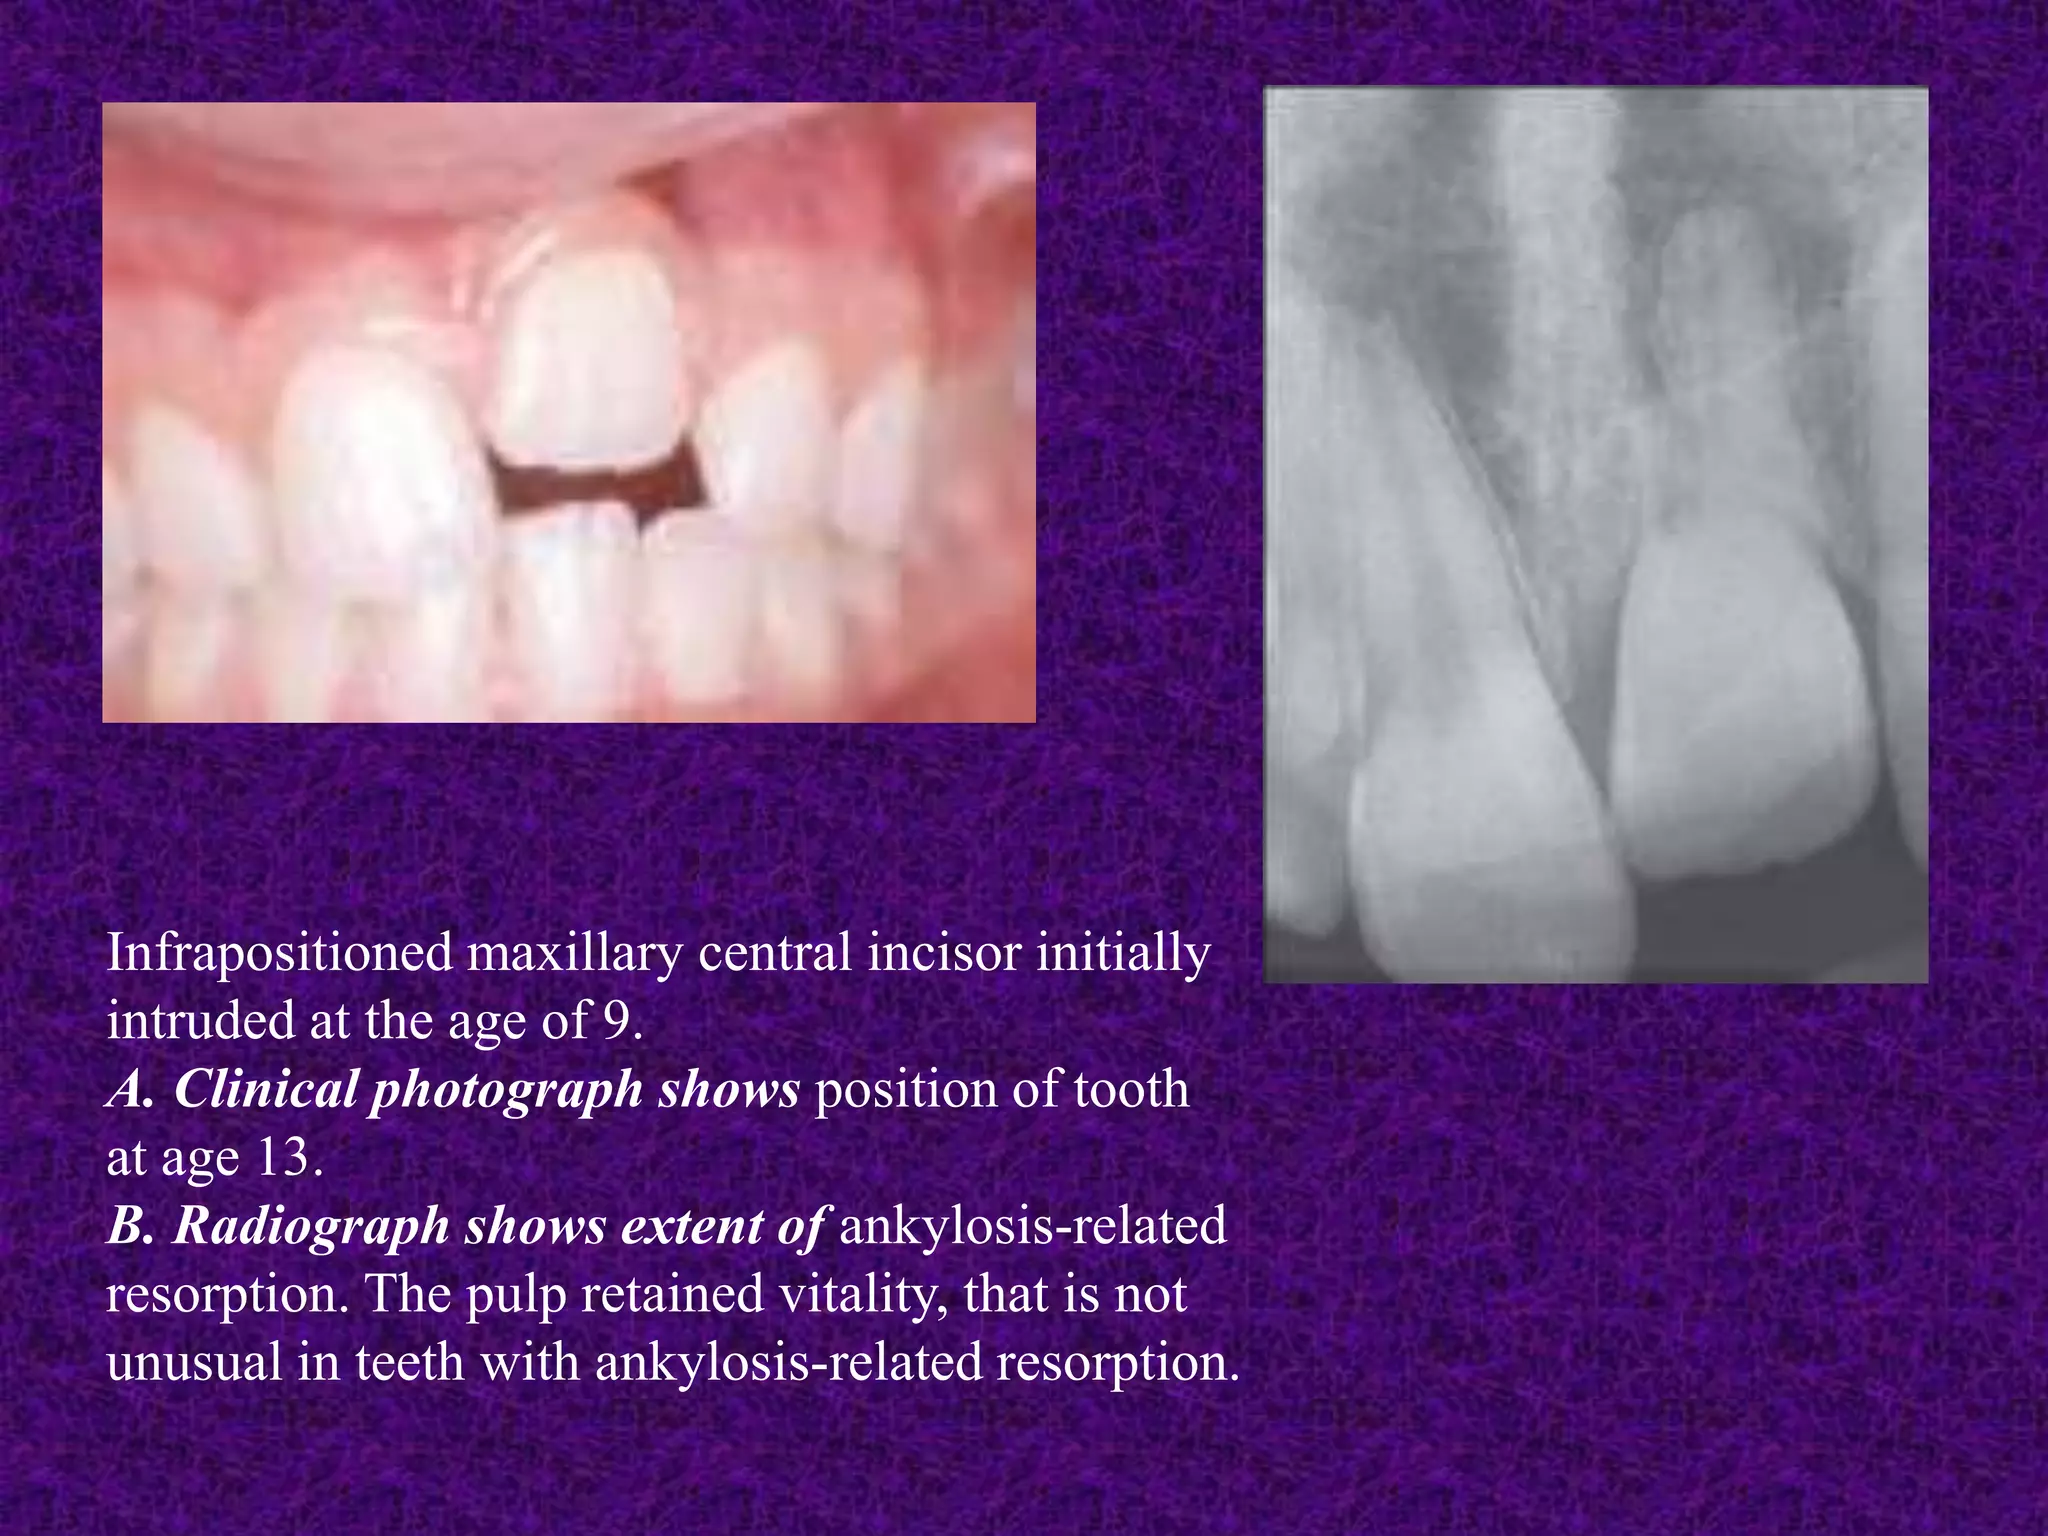

Fig: External spontaneous ankylosis resorption.

A. Graphic illustration. B. Clinical example

INGLE’S ENDODONTICS 7TH ED. PAGE-

421-437